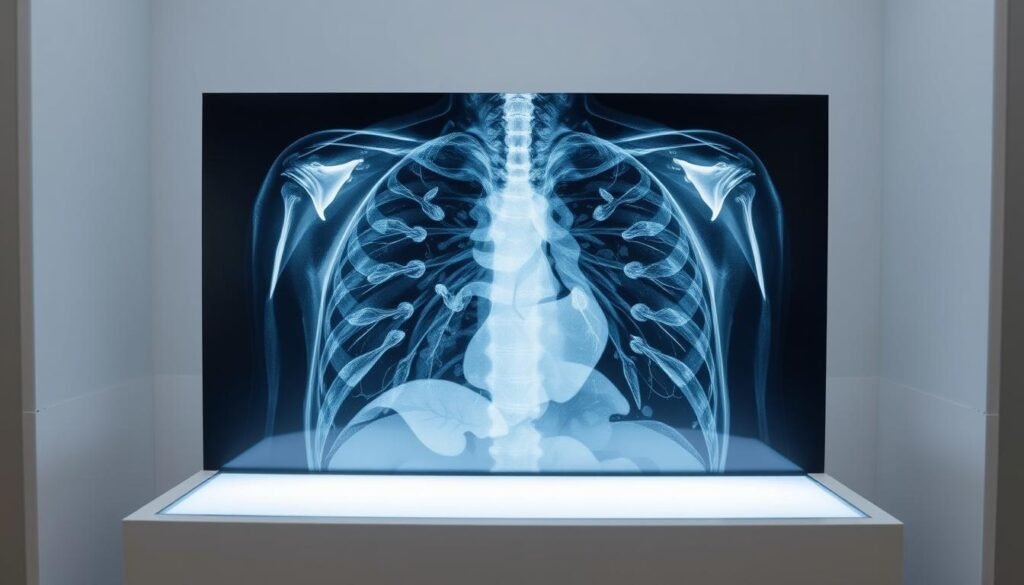

Le scanner thoracique est un examen d’imagerie médicale essentiel pour diagnostiquer diverses pathologies pulmonaires. Utilisant des rayons X à faible dose, il permet d’obtenir des images précises en coupe du thorax. Cet outil est particulièrement efficace pour détecter précocement des maladies graves comme le cancer du poumon, première cause de décès par cancer en France.

Comparé à une radiographie standard, cet examen offre une meilleure résolution. Il aide les médecins à identifier des anomalies invisibles sur d’autres types d’images. Son rôle est crucial dans le suivi des patients à risque ou présentant des symptômes inquiétants.

Cet examen repose sur un faisceau de rayons X rotatif, capturant des coupes transversales du thorax. Il combine précision et rapidité pour analyser les structures internes.

La technique d’imagerie médicale permet de visualiser les poumons, le cœur, et même les plus petits vaisseaux sanguins. Elle identifie des lésions inférieures à 5 mm, comme des nodules précoces.

Différence avec une radiographie standard

Contrairement à une radiographie classique, cet outil offre une résolution 10 à 15 fois supérieure. Les images en coupe éliminent les superpositions d’organes.